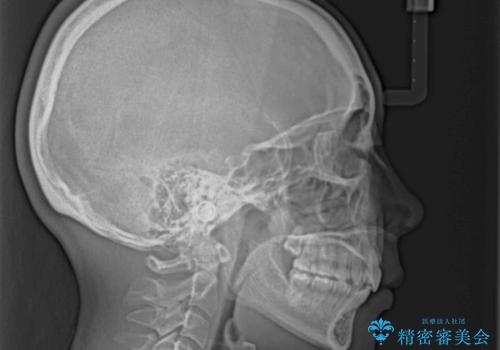

上顎前突で口が閉じにくい ワイヤー装置での抜歯矯正

ご本人がびっくりするくらい劇的に口元の突出感が改善され、大変満足のいく仕上がりとなりました。